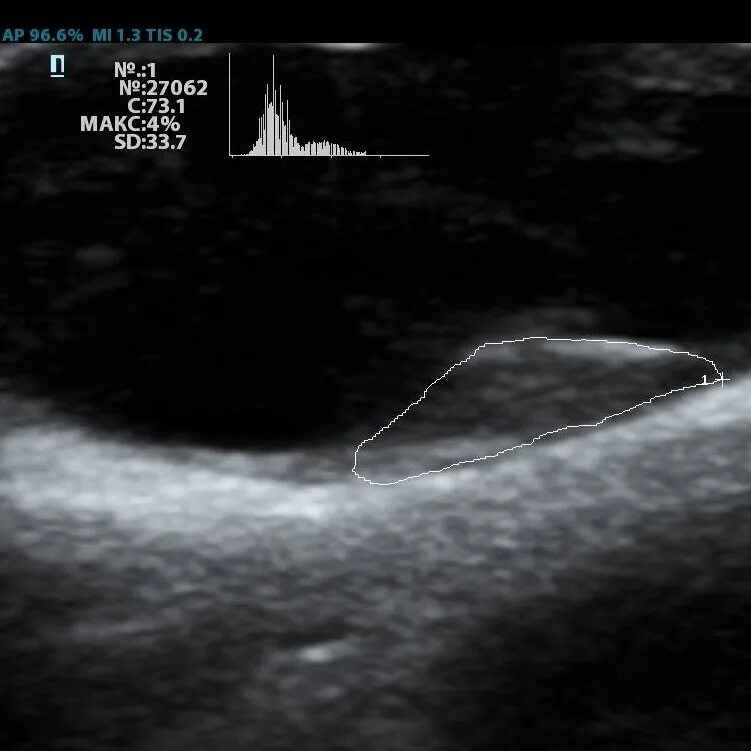

Атеросклеротическая бляшка узи